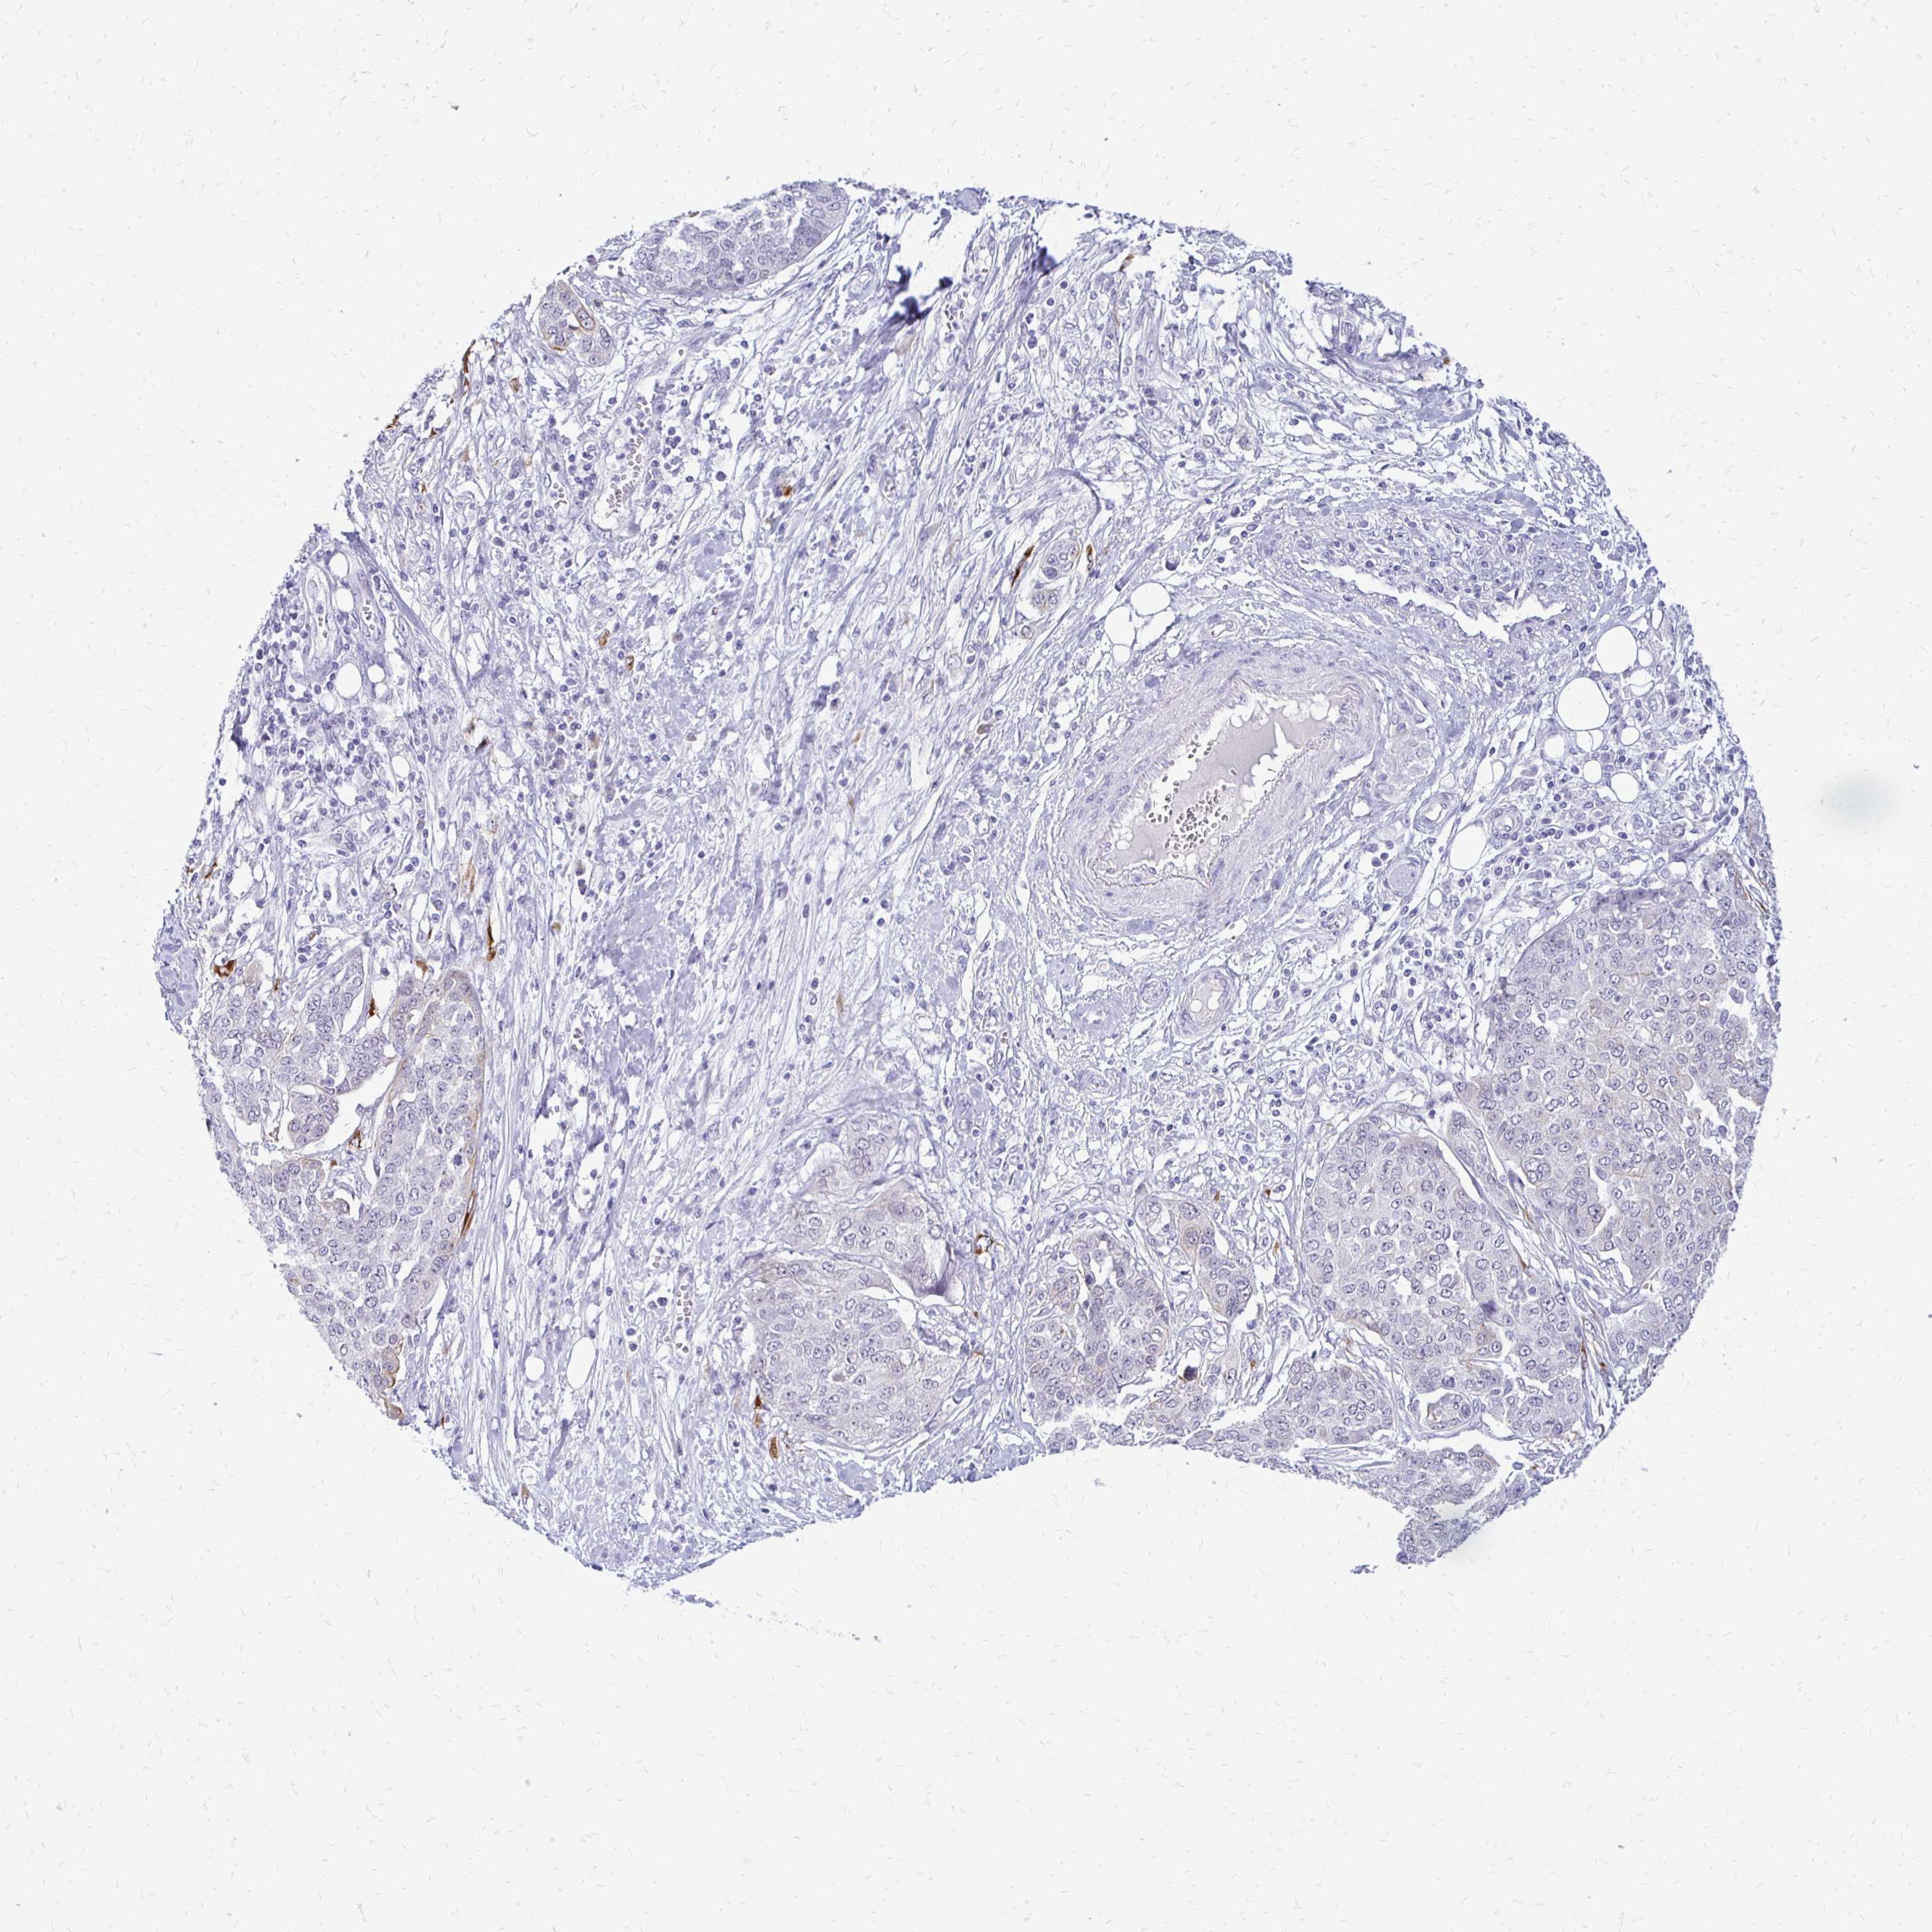

OVARIAN CANCER - Protein expressioni

A mouse-over function shows sample information and annotation data. Click on an image to view it in a full screen mode. Samples can be filtered based on level of antibody staining by selecting one or several of the following categories: high, medium, low and not detected. The assay and annotation is described here.

Note that samples used for immunohistochemistry by the Human Protein Atlas do not correspond to samples in the TCGA dataset.

Antibody stainingi

Antibody staining in the annotated cell types in the current human tissue is reported as not detected, low, medium, or high, based on conventional immunohistochemistry profiling in selected tissues. This score is based on the combination of the staining intensity and fraction of stained cells.

Each image is clickable and will lead to virtual microscopy that enables deeper exploration of all samples and also displays staining intensity scores, fraction scores and subcellular localization as well as patient and tissue information for each sample.

Antibody HPA038212

Antibody HPA045455

Cystadenocarcinoma, serous, NOS

Carcinoma, endometroid

Cystadenocarcinoma, mucinous, NOS

Carcinoma, NOS